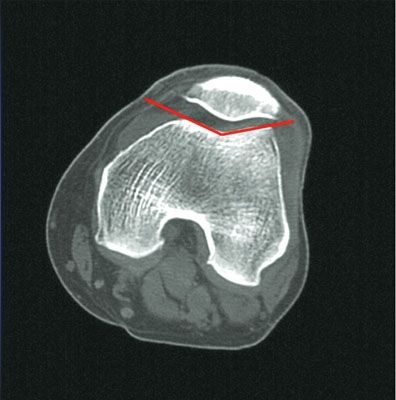

Actualité Différences anatomiques homme-femme au niveau de l'extrêmité distale du fémur et applications cliniques. , Sébastien Parratte Centre de Chirurgie de l’Arthrose, Hôpital Sainte Marguerite, Université Aix-Marseille II, Marseille, France , M. Mahfouz Center for Musculoskeletal research, University of Tennessee, Knoxville, TN, USA , Robert Booth Pennsylvania Hospital, University of Pennsylvania, Philadelphia, PA, Etats-Unis , Jean-Noël Argenson Centre de Chirurgie de l’Arthrose - Hôpital Sainte Marguerite, Université Aix-Marseille II, Marseille, France N°158 - Novembre 2006 ● 18 min de lecture